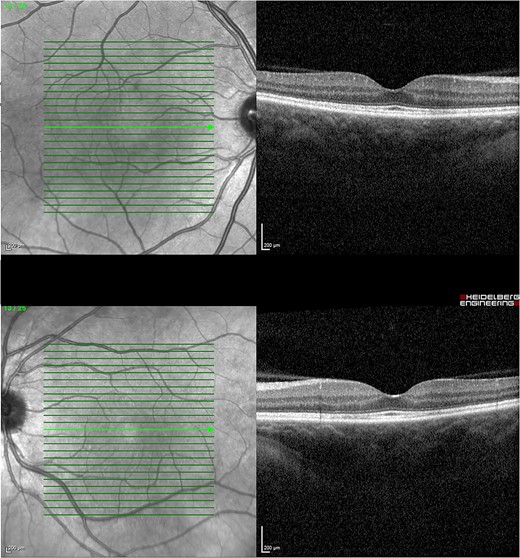

One week after initial review, the patient presented with eye casualty with deteriorated vision of 6/9 in the right eye and count fingers in the left eye. Intraocular pressure was within normal limits in both eyes. Anterior segment examination showed mild anterior uveitis with mild conjunctival injection, 1+ cells in the right eye, 2+ cells in the left eye, and 0.5+ cells in the anterior vitreous of both eyes. No keratic precipitants or posterior synechiae were present in either eye. Fundoscopy revealed bilateral hyperemic discs and 360° choroidal detachments with serous retinal detachment involving the maculae (Fig. 1). There was no evidence of vitritis or retinitis. OCT illustrated detachments of the neurosensory retina and bacillary layers (Fig. 2). Fundus fluorescein angiogram (FFA) demonstrated bilateral disk hyperfluorecence, macular hyperfluorescent pinpoints, and no evidence of retinal vasculitis or ischemia (Fig. 3).

OCT 1 week after initial presentation illustrating neurosensory retinal and bacillary layer detachments, retinal pigment epithelium folds, and darkened choroid pathognomonic for VKH.

Given the clinical features, the patient was diagnosed with VKH-like syndrome, presumably secondary to MEK and BRAF inhibitor therapy. In consultation with her oncologist, dabrafenib and trametinib were withheld. She was admitted and promptly started on pulsed methylprednisolone 1 g daily for 3 days. Autoimmune and infective screens were all negative. Magnetic resonance imaging of the brain with contrast had no evidence of cerebral vasculitis. The patient responded well to methylprednisolone with BCVA of 6/9–1 in the right eye and 6/30 in the left after 3 days. Subsequently, she was started on a slow tapering dose of oral prednisolone of 5 mg weekly with a starting dose of 65 mg daily. In conjunction with the oncologist, dabrafenib was reintroduced at 150 mg twice daily after being withheld for 2 weeks. Trametinib was reintroduced at a lower dose of 0.5 mg daily and was slowly up titrated to 1 mg after being withheld for 4 weeks. Her BCVA and OCT were monitored monthly, illustrating a progressive decline in ONHS and subretinal macular fluid. Four months later, her BCVA recovered to 6/6 in both eyes with no evidence of active uveitis and completely resolved subretinal fluid while on a maintenance dose of 10 mg prednisolone daily (Fig. 4).

OCT 4 months post treatment showed complete resolution of fluid and reinstitution of normal retinal architecture.